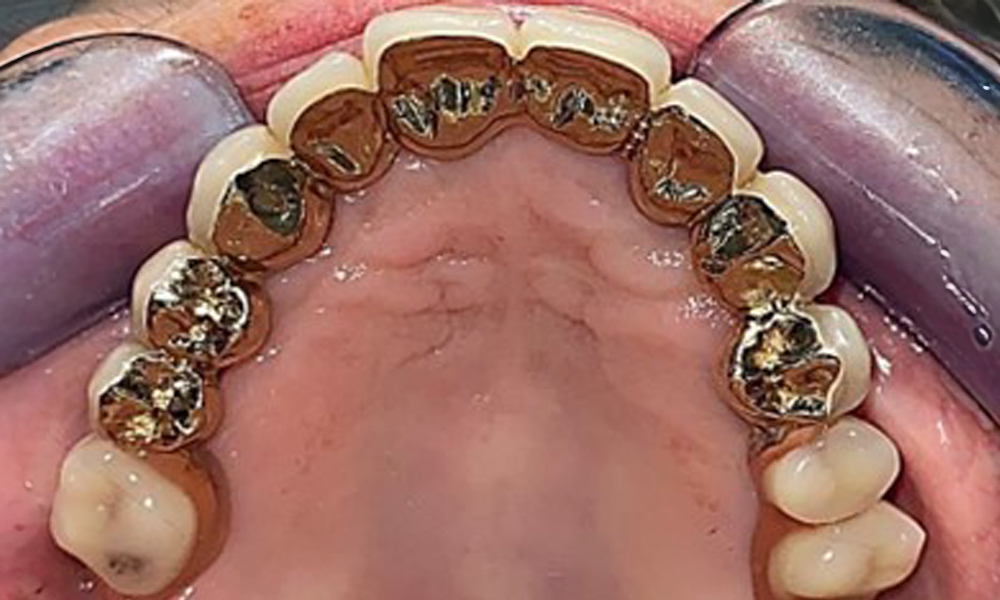

На пациентката е поставена комбинирана подвижна горночелюстна телескопична протеза преди повече от 25 години (фиг. 1, фиг. 2, фиг. 3) и тя е много доволна от протезите си. Пациентката има адекватна фиксирана протеза за долната челюст (фиг. 4).

Денталните открития са следните: Комбинирани снемаеми протези на импланти и телескопични протези, поддържани от зъби, на импланти 15, 13, 21, 23, 24, 25 и зъб 11 (фиг. 1, фиг. 2, фиг. 3). Пациентът е снабден с фиксирана долночелюстна протеза. Над зъби 37-34 и 45-47 бяха налични адекватни мостове (фиг. 4), краищата на коронките бяха интактни и нямаше активен кариес. Върху зъб 43 имаше композитна пломба с маргинална празнина. Имаше рецесия на долната гингива, която разкриваше от 1 до 3 mm от кореновата повърхност. Това се отнася и за 11.